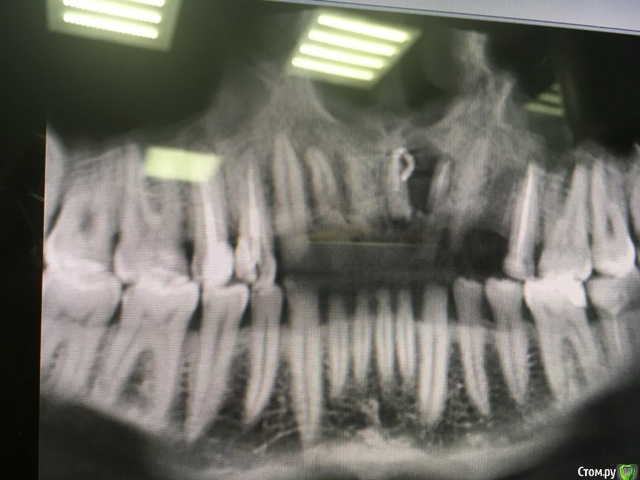

Astronaft Опубликовано 6 июля, 2018 Поделиться Опубликовано 6 июля, 2018 (изменено) Я пробовал один раз.Впечатления смешанные.1. просто в исполнении.2. Хорошо, быстро заживает. Есть ощущение что так можно проводить профилактику альвеолита.3 .Десны действительно достаточо.4. Кость - неоднозначно. Надо попробовать 2 рядом стоящих зуба "с шайбой" и "без".5. Шайба удаляется легко. Без анестетика, зондом поддел.6. Поверхность под шайбой - белая соед.тканная пленка. Рентген в день удаления -> фото через неделю -> фото через 2 месяца + КЛКТ ( срезы: перегородка и оба корня) http://miworks.weebly.com/uploads/1/6/8/7/16879370/x07221.jpg http://miworks.weebly.com/uploads/1/6/8/7/16879370/dscn6666_orig.jpg http://miworks.weebly.com/uploads/1/6/8/7/16879370/dscn6948_orig.jpg http://miworks.weebly.com/uploads/1/6/8/7/16879370/dscn6943_orig.jpg http://miworks.weebly.com/uploads/1/6/8/7/16879370/dscn6952_orig.jpg http://miworks.weebly.com/uploads/1/6/8/7/16879370/dscn6953.jpg http://miworks.weebly.com/uploads/1/6/8/7/16879370/dscn6954.jpg http://miworks.weebly.com/uploads/1/6/8/7/16879370/dscn6949_orig.jpg http://miworks.weebly.com/uploads/1/6/8/7/16879370/x07221-1.jpghttp://miworks.weebly.com/uploads/1/6/8/7/16879370/x07221-4.jpg http://miworks.weebly.com/uploads/1/6/8/7/16879370/x07221-2.jpghttp://miworks.weebly.com/uploads/1/6/8/7/16879370/x07221-3.jpg Изменено 6 июля, 2018 пользователем Astronaft 4 Ссылка на комментарий

kamranchick Опубликовано 6 июля, 2018 Поделиться Опубликовано 6 июля, 2018 Я думаю если аккуратно удалить зуб, похожий результат будет(Ну по моим наблюдениям.У Вас Астронафт мне кажется также наверное все бы восстановилось бы, судя по первому прицельному RVG 1 Ссылка на комментарий